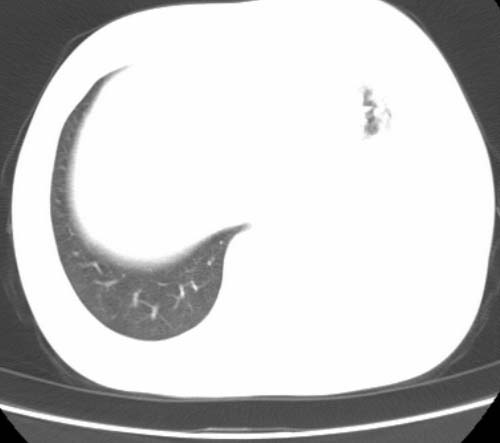

标题: CT25648:求教:是肺发育不全还是结核?

女  20岁。一月前咳血,诊“肺结核”抗痨治疗一月后,咳血停止,现复查。病人精神好。前后ct片对比未见明显变化。既往体检“正常”

1)考虑左肺结核并肺不张、支气管扩张。2)纵隔疝。

考虑左肺结核,左肺毁损,纵膈左偏,既往体检正常不可靠,tb一个月也不会这个样子的,有钙化,应该病程较长,冰冻三尺非一日之寒!

左肺发育不全。